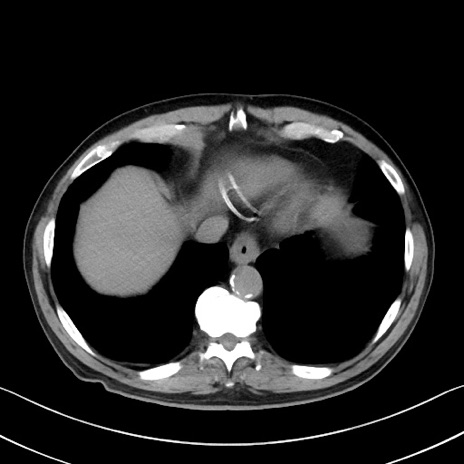

症例35(横断像)

【症例】70歳代 男性

【主訴】腹部膨満、嘔吐

【現病歴】昨日より腹部膨満感出現。本日増悪し、仙痛出現。嘔吐あり、受診。

【既往歴】糖尿病、胆摘後

【身体所見】BP 149/80mmHg、HR 74/min、BT 35.9℃、腹部:膨満、軟、圧痛なし。腸雑音減弱あり。上腹部正中切開瘢痕あり。

【データ】WBC 13500、CRP 1.72